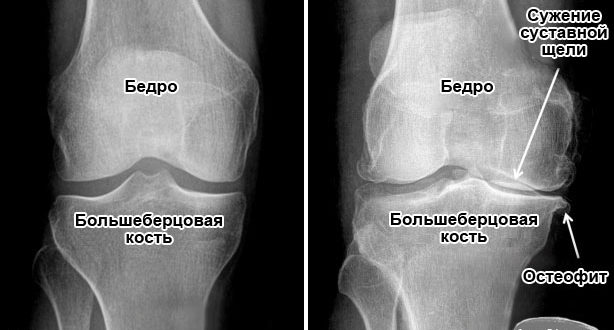

Диагностика остеоартроза Диагноз может быть выставлен на первом приеме у ортопеда на основании внешнего осмотра, описания пациентов характерных признаков остеоартроза, данных анамнеза. Для его подтверждения и исключения заболеваний…